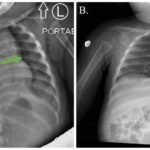

Congenital diaphragmatic hernia is usually diagnosed prenatally and surgically repaired within the first few days of life. It is very rarely associated with acute gastric volvulus, an uncommon surgical emergency in children. A male infant with atypical presentation of acute gastric volvulus was diagnosed and treated by a swift-acting team across two medical centers. The patient presented with generalized abdominal distention and non-productive retching. Upper gastrointestinal series diagnosed acute gastric volvulus. During laparoscopic intervention, the volvulized stomach and the spleen were identified within an undiagnosed congenital diaphragmatic hernia. Corrective surgery was performed, and the patient tolerated a regular diet within days and continues to do well. Given the emergent nature of acute gastric volvulus in children, a high index of suspicion is warranted to quickly initiate potentially life-saving diagnostics and treatment.